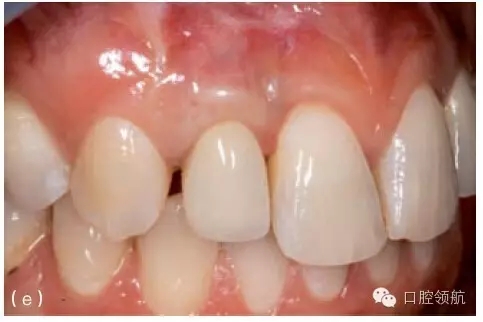

圖8.23 (a)右上頜側(cè)切牙(7號(hào)位點(diǎn))種植體和冠初診時(shí)情況。約有3mm的黏膜退縮,種植體金屬領(lǐng)圈暴露。(b)第一步,拆下冠和基臺(tái),讓種植體2周時(shí)間的自然愈合。(c)做半厚瓣翻瓣,結(jié)締組織移植至種植體并進(jìn)行瓣的冠向復(fù)位。面觀顯示4周的愈合期后種植體完全埋在黏膜下。(d)做小切口,足以安裝錐形基臺(tái)即可。(e)治療和粘結(jié)新冠3年后,原先的黏膜退縮已成功恢復(fù),組織健康穩(wěn)定。

圖8.25 (a)右上頜側(cè)切牙(7號(hào)位點(diǎn))種植體唇側(cè)黏膜退縮。種植體有唇側(cè)植入位置不佳。(b)拆下冠和基臺(tái)并以暫時(shí)的局部義齒修復(fù)后的臨床情況。局部義齒選取正確的冠長(zhǎng)度,顯示出軟組織垂直向缺損。(c) 牙合面觀:拆下冠和基臺(tái),安裝愈合基臺(tái)。清楚可見(jiàn)種植體唇側(cè)植入位置不佳。(d)做頰側(cè)全厚瓣翻瓣,可見(jiàn)牙槽嵴骨水平與種植體相對(duì)關(guān)系算是常規(guī)位置。(e)從腭側(cè)獲取結(jié)締組織瓣,覆蓋種植體唇側(cè)與牙合面。(f)唇面觀:瓣關(guān)閉縫合后,暫時(shí)局部義齒修復(fù)。(g)術(shù)后2個(gè)月,結(jié)締組織移植瓣已完全與周圍組織融合,種植體完全覆蓋。(h)牙槽嵴頂做小切口暴露種植體頂端,安裝一個(gè)選磨過(guò)的愈合基臺(tái)。(i)種植體粘結(jié)暫時(shí)冠。原來(lái)退縮的程度有所減小,但是完全恢復(fù)軟組織的高度沒(méi)有實(shí)現(xiàn)。種植體唇側(cè)植入位置不佳時(shí),恢復(fù)的軟組織垂直高度有限。